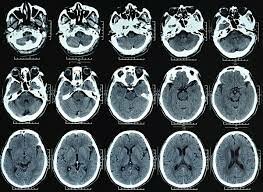

A partir de esta época el contenido de la neuropsicología cambio debido a:

1. equipos tecnológicos incorporados, como la tomografía axial (TAC)